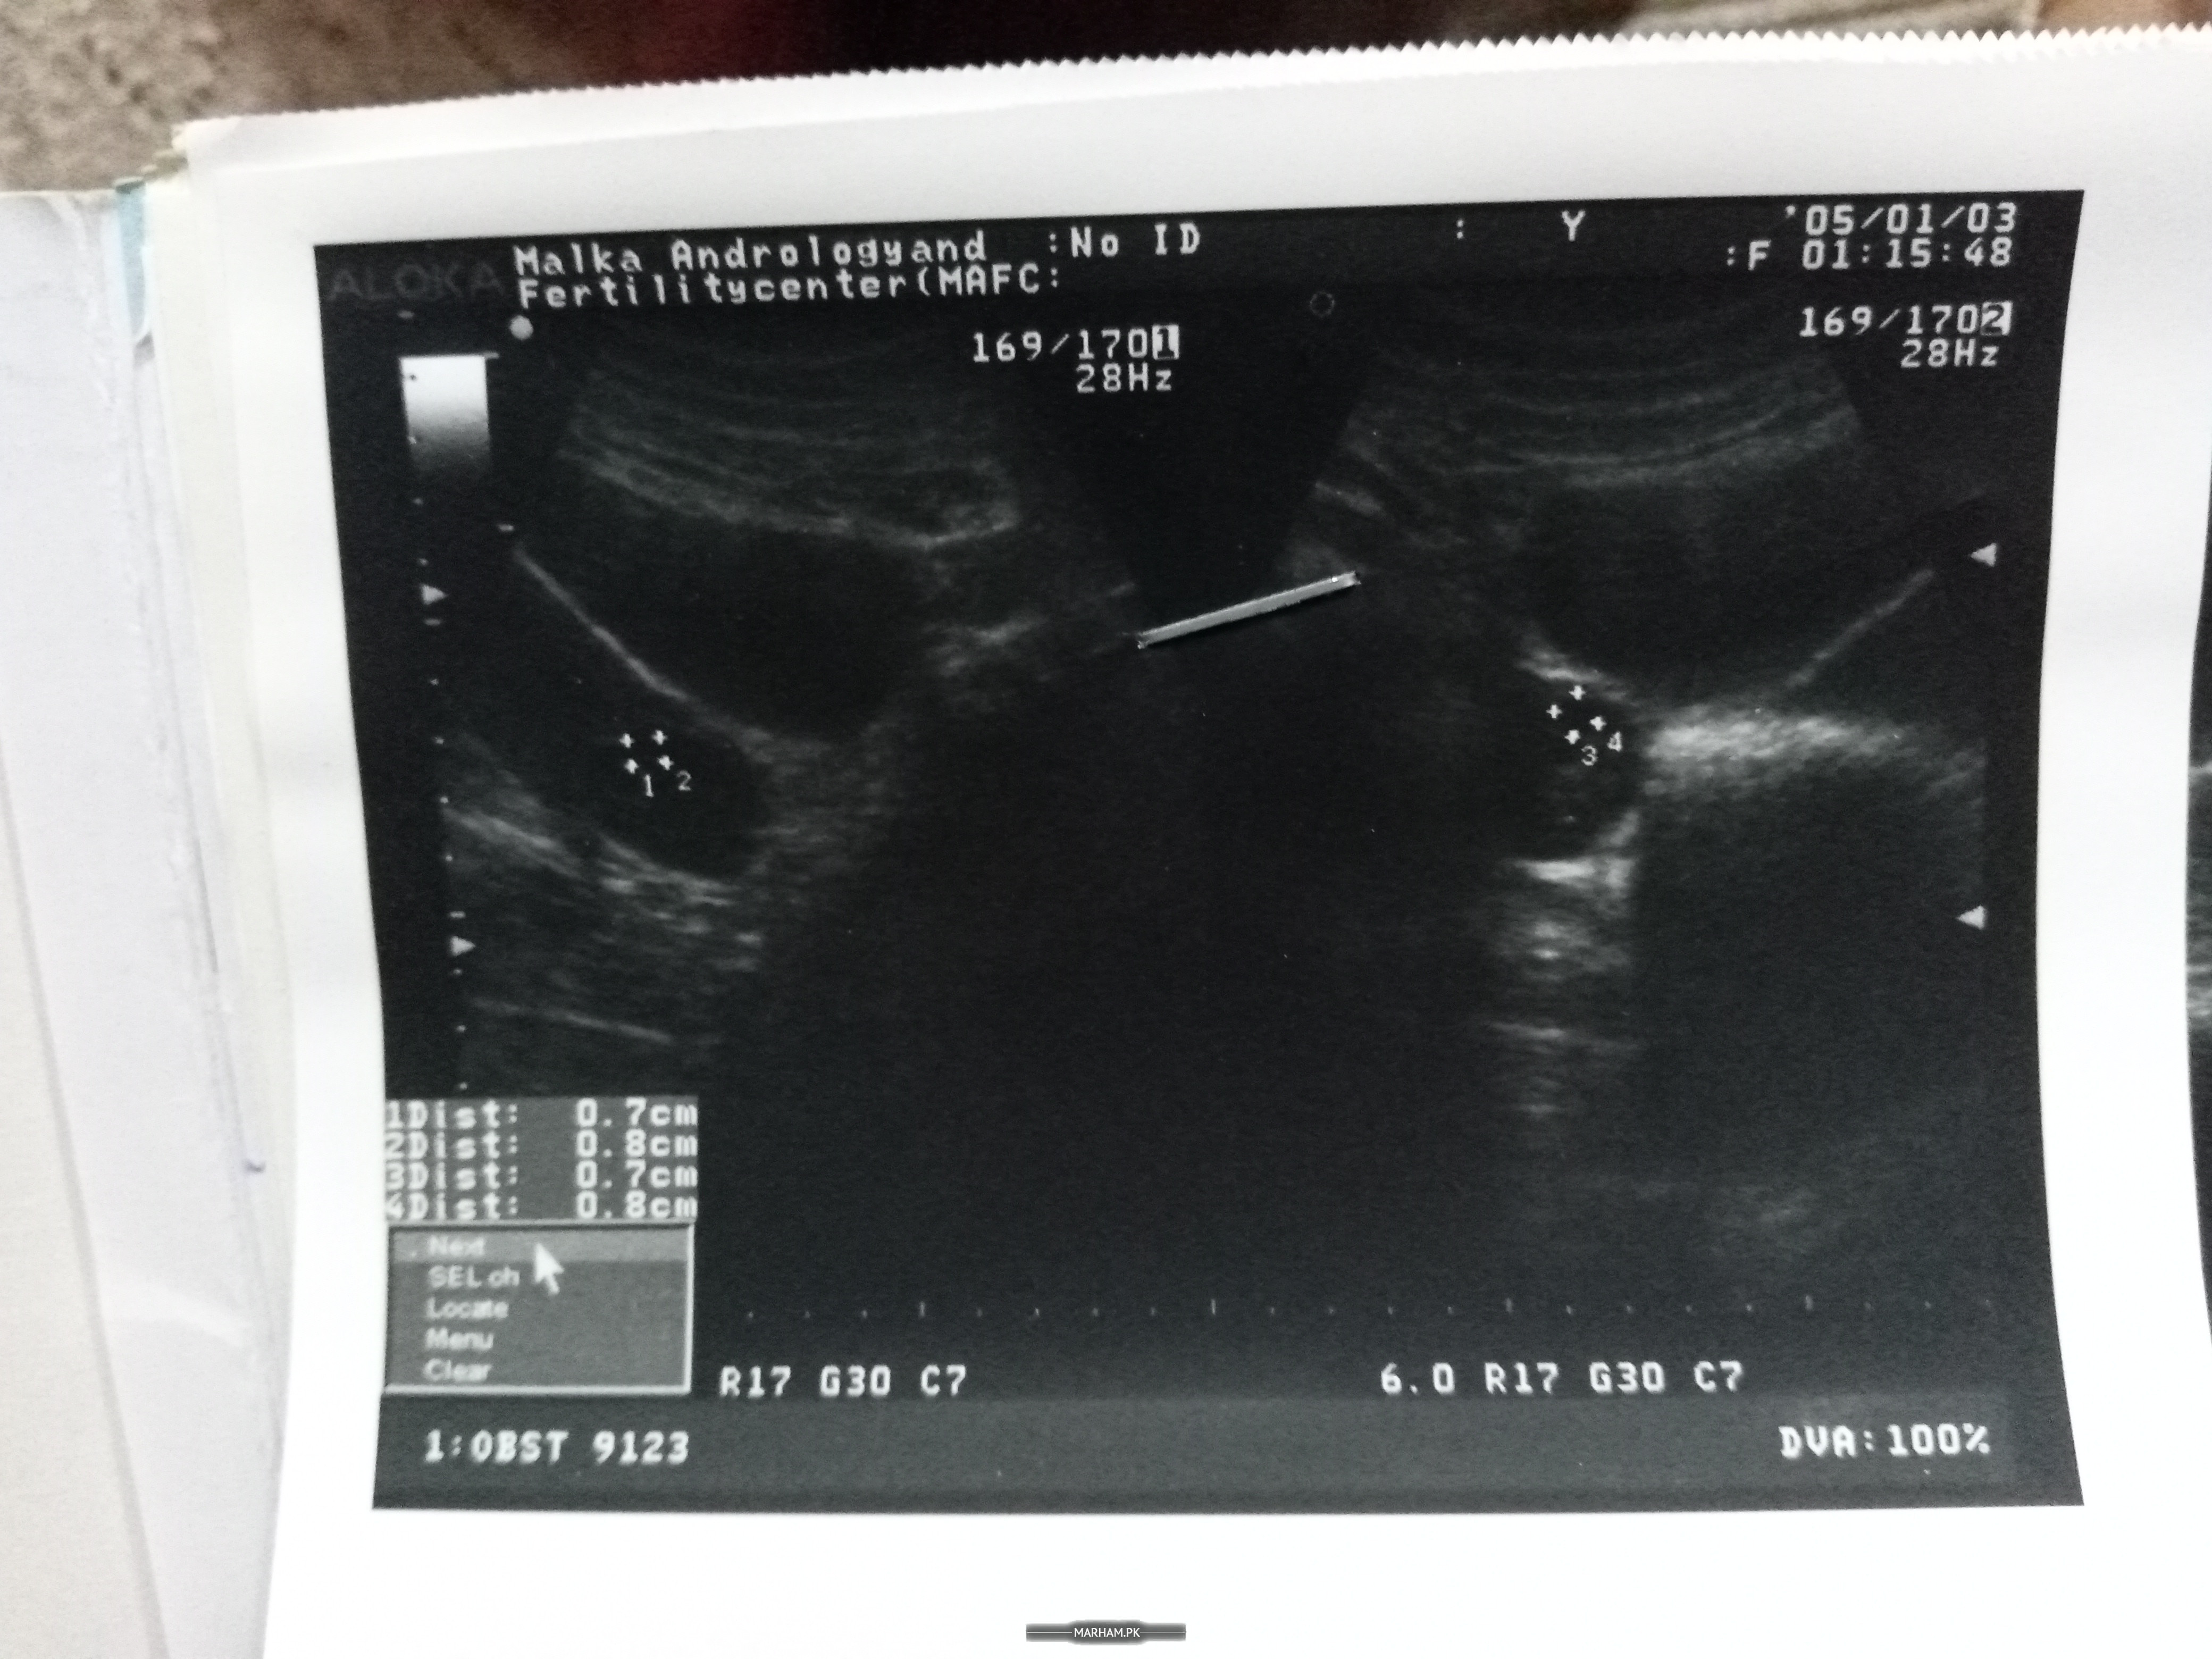

jo bhi test krwaye hyn share kry

Attach Photo here: